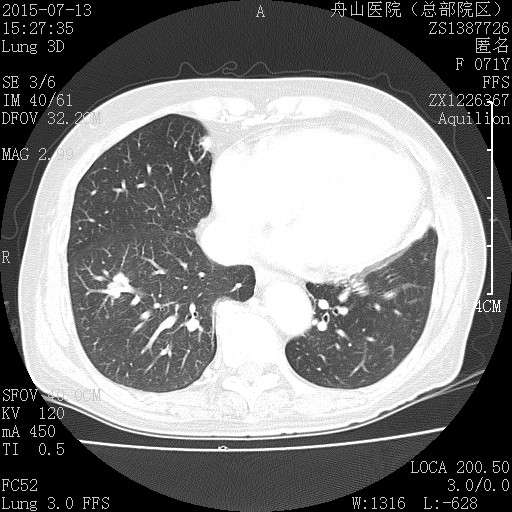

许多小白球--隐球菌,不做PAS及六铵银特染也看得清 荚膜的感觉明显 第三例的CT